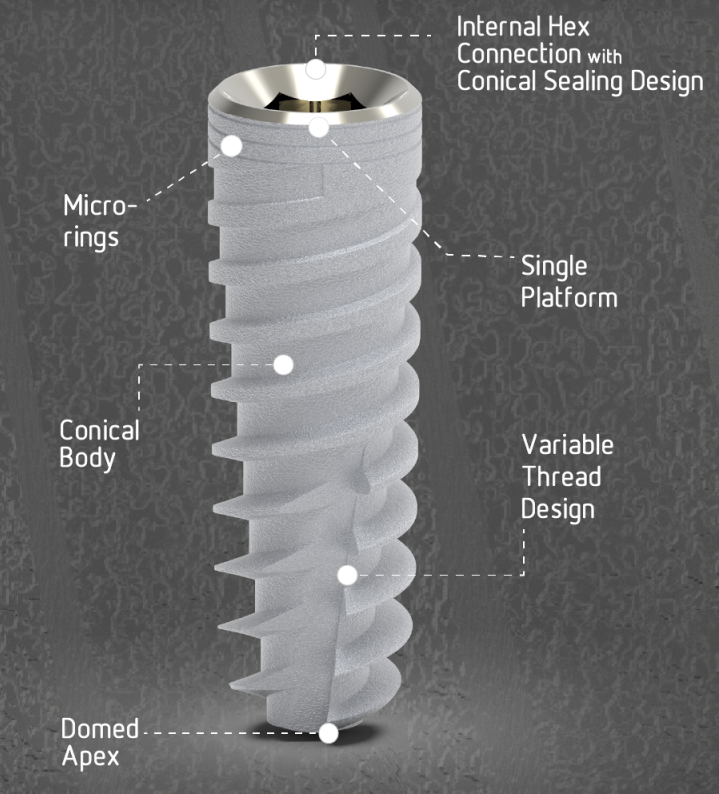

AlfaGate Dental Implants Collection

زرعات فردية

زرعات تيتانيوم فردية لتعويض سن واحد مفقود